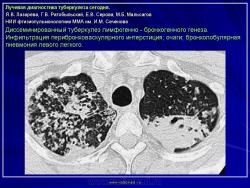

Лучевая диагностика туберкулеза сегодня

Я.В. Лазарева, Г.В. Ратобыльский, Е.В. Серова, М.Б. Мальсагов

НИИ фтизиопульмонологиии ММА им. И.М. Сеченова